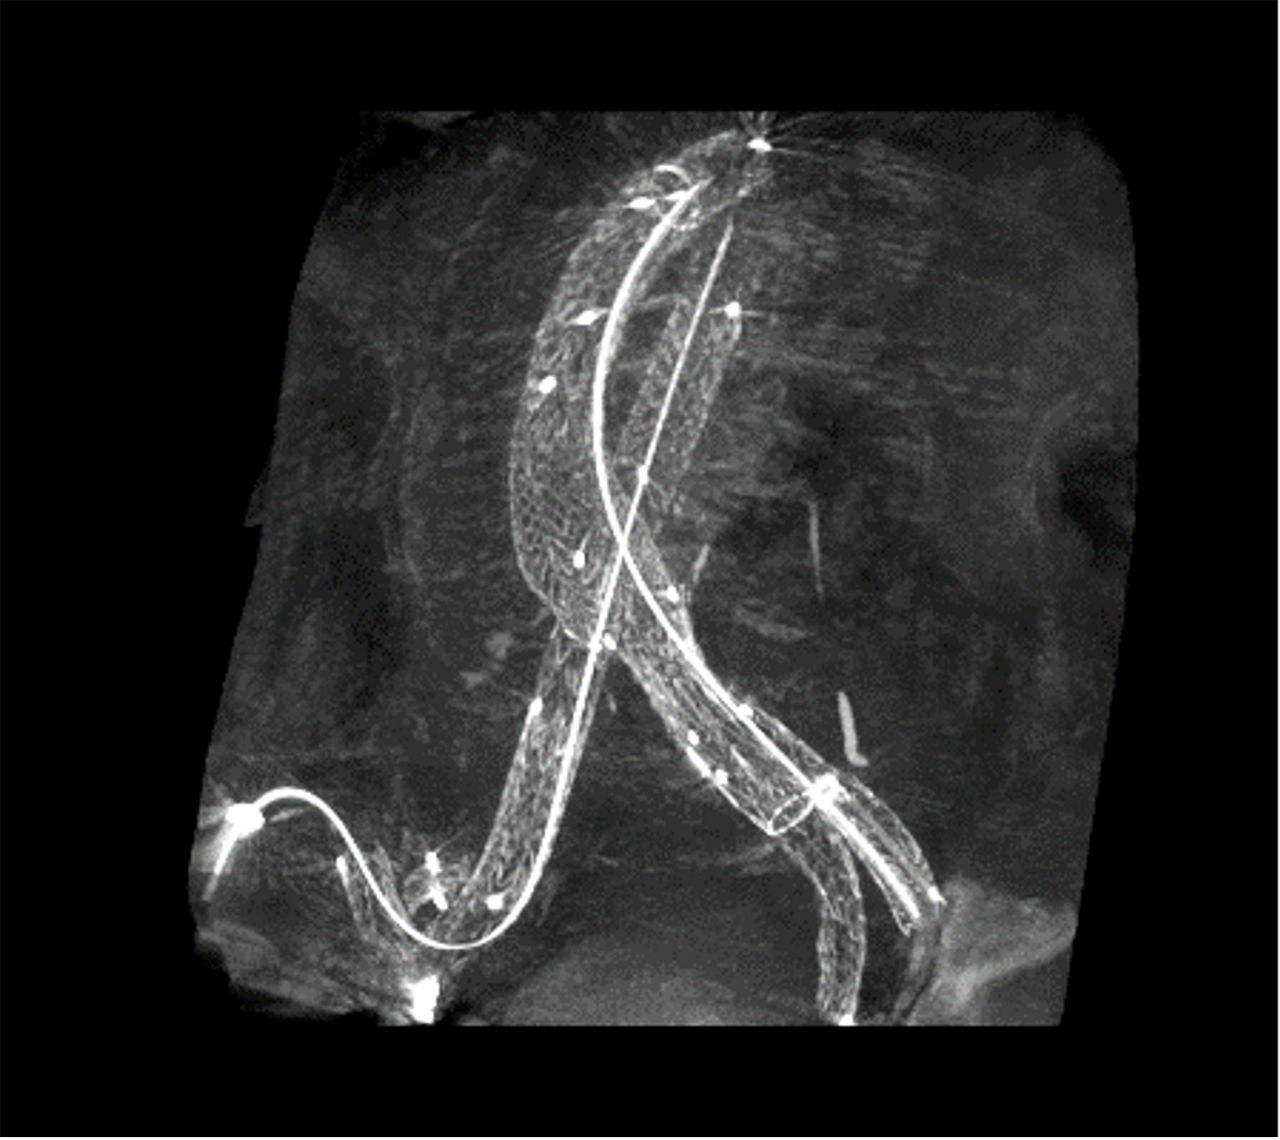

Volumetric images acquired with OEC 3D at the end of the procedure

The Volume Viewer displays 5 volumetric images on the monitor screens: cross sectional planes (axial, coronal, sagittal), volume rendering (VR) and maximum intensity projection (MIP).

The Volume Viewer’s tools enable the user to choose the display mode options and several tools for viewing images of cross-sectional planes (such as Multi Oblique Mode, scrolling through slices, slice thickness adjustment, window level, zoom, measurement, annotation and image storing). For VR and MIP images it also allows users to rotate the image.

The procedure included the embolization of the distal branches of the left hypogastric artery and the implantation of a bifurcated infrarenal stent graft with a left external iliac extension covering the origin of the hypogastric artery. The embolization enclosed the implantation of an Amplatzer AVP2 plug (Abbott) in one of the main distal branches of the hypogastric and was completed by pushable coils in other small branches [Concerto coils (Medtronic)]. Subsequently, after visualization of the lowest renal artery with a CO2 aortography (volume and flowrate to be provided and administrated by the Angiodroid injector (Bologna, Italy)), a bifurcated infrarenal stent graft (RLT261412, Gore) was implanted. A final 2D angiography (25cc of ICM at a 15cc/sec) to assess the patency of the stent graft and potential perigraft leak was performed. A mobile CBCT scan using the high-definition mode of the OEC 3D was completed additionally and depicted constraints by the aorto iliac native bifurcation on both limbs of the stent graft requiring additional kissing stent (BeSmooth, Bentley).